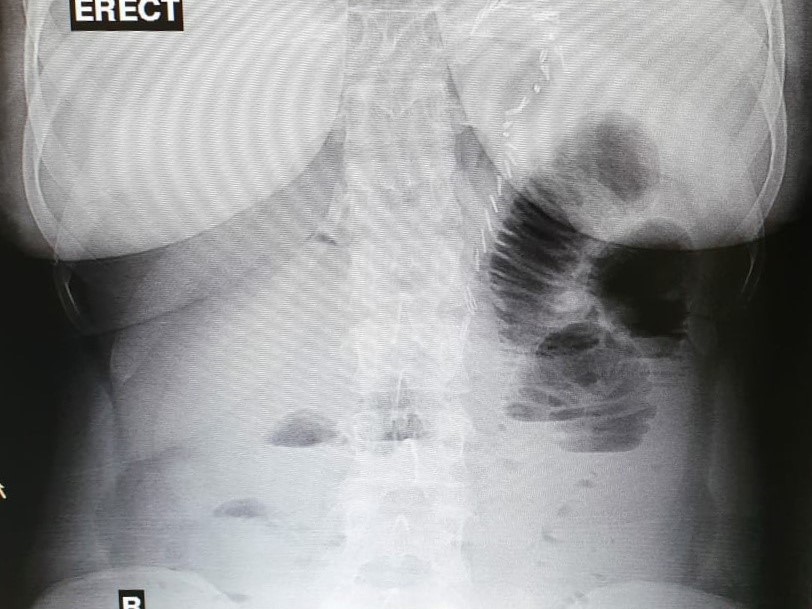

From radiopaedia.org

Hiatal hernia after sleeve gastrectomy Image Hernia After Sleeve Surgery Managing and preventing hiatal hernia after gastric sleeve surgery involves a combination of lifestyle modifications, medications, and, in some cases, surgical. When properly performed, bariatric patients experience a reflux free weight loss journey. It is a safe procedure that rarely presents complications, with the most common being bleeding or staple line leaks. It also discusses ways to prevent complications, as. Hernia After Sleeve Surgery.

Hiatal hernia after sleeve gastrectomy Image Hernia After Sleeve Surgery All my surgeon did was hernia repair with a. This article will help you understand what to expect 10 years after gastric sleeve surgery, also known as sleeve gastrectomy. Gregory dumanian is a board. After two endoscopies and barium swallows, the surgeon says i have a type 3 hiatal hernia now. When properly performed, bariatric patients experience a reflux free. Hernia After Sleeve Surgery.